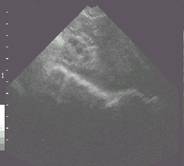

Probe Position

Place probe against flank. Aim just behind opposite shoulder and slowly rotate hand backwards.